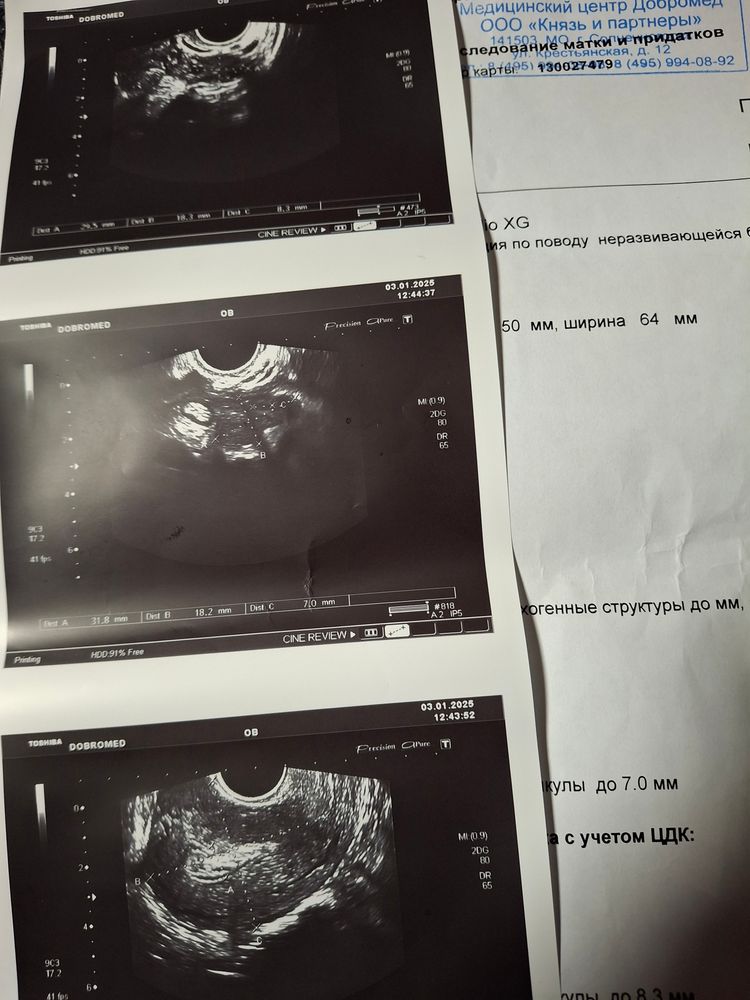

Пишу для себя и для тех, кто тоже ищет как проходит вакуумная чистка в 15ой больнице Выхино по направлению из женской консультации. В жк в новогиреево 19 ноября по узи эмбриональный срок был 6 недель 6 дней, даже услышали сердцебиение 140 ударов. 30 ноября днем пошли коричневые выделения, а ночью немного кровило. 1 декабря рано утром сходила на узи